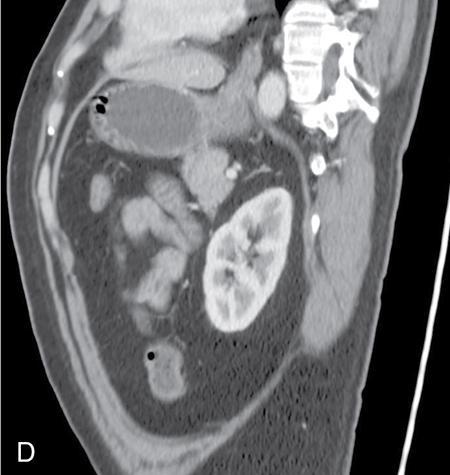

Amit Kumar Kamble, Abhinav Ranwaka The adult urinary system is formed of a pair of kidneys, a pair of ureters, a urinary bladder and a urethra. All these structures are extraperitoneal in location and extend from upper abdomen to the pelvis and into the exterior. These organs can be visualised on a host of imaging modalities, and a knowledge of these appearances helps the radiologist identify the relevant pathologies. Having a complex embryological development, the urinary system can have a wide spectrum of normal and abnormal anatomical variants. This chapter describes the appearance of the urinary system in commonly used imaging modalities and their common variants. Kidneys are paired bean-shaped structures situated in the retroperitoneum on either side of the vertebral column. The kidney consists of The renal sinus contains: The kidneys are surrounded by the renal capsule which is enclosed in the perirenal space. This space predominantly contains the perinephric fat and has thin septations within (Kunin’s septa); these septae may be thickened in various renal pathologies seen as perinephric stranding on imaging. The perirenal space is bounded by the perirenal fasciae, called the Gerota fascia (anterior perirenal fascia) and Zuckerkandl fascia (posterior perirenal fascia). The leaves of perirenal fascia fuse superiorly, laterally and medially. Superiorly, the perirenal fasciae also enclose the adrenal gland, which is separated from the kidney by a septum (Fig. 10.2.2). The anterior and posterior perirenal fasciae fuse laterally to form the lateral conal fascia. Medially, the perirenal fascia also encloses the renal pedicle. Medially, it communicates with renal sinus fat. There may be the communication of perirenal spaces across the midline. Superiorly, the perirenal space communicates with the bare area of the liver or spleen. The ureter arises from the perirenal space and travels inferiorly in anterior pararenal space. Inferiorly, the perinephric space may communicate with periureteric tissues. Interfascial planes are potential planes in between the leaves of the anterior perirenal fascia, called the retromesenteric plane and in the anterior perirenal fascia called the retrorenal plane. Anterior pararenal space: It is bounded by parietal peritoneum anteriorly, anterior perirenal fascia (Gerota) posteriorly and lateral conal fascia laterally. The anterior pararenal space contains the pancreas, second and third part of the duodenum, the retroperitoneal segments of ascending and descending colon and the roots of the small bowel mesentery and transverse mesocolon. Posterior pararenal space: It is bounded by posterior perirenal fascia (Zuckerkandl) anteriorly, fascia transversalis posteriorly and lateral conal fascia laterally. Caudally, the pararenal spaces communicate with each other and also with the extraperitoneal spaces. All the three spaces communicate at the pelvic brim. Understanding of the anatomy of spaces around the kidney is important for local staging of renal pathologies. Renal arteries are the branches of abdominal aorta. They originate laterally from the aorta below the origin of superior mesenteric artery. Accessory unilateral renal artery occurs in 30% of the population and bilaterally in 10% of population. Renal artery is divided into anterior division, which divides into four segmental branches and a posterior division; these arteries are end arteries supplying the respective segments of the kidneys (Fig. 10.2.3): apical, upper, middle, lower segments supplied by the anterior division, and a posterior segment supplied by the posterior division. The segmental arteries divide into lobar branches one to each to renal pyramid. Before reaching to pyramid, they divide into two to three interlobar branches. At the junction of cortex and medulla, interlobar arteries divide into arcuate arteries at the right angle. They further subdivide into interlobular artery, afferent and efferent arterioles. The efferent arteriole drains into peritubular plexus. The plane where the branches of the anterior and posterior divisions meet is located between the anterior two-thirds and posterior one-third of the kidney and is relatively avascular; it is called the avascular plane of Brodel (Fig. 10.2.3), and is a relatively safe site for nephrostomy access. Peritubular plexus converges to form the interlobular vein. These veins accompany their arterial counterparts and drain into the renal vein. The renal veins are situated anteriorly to the renal arteries and finally drain into the inferior vena cava at the right angles (Fig. 10.2.4). The two left renal veins may be present one passing anterior and other posterior to the aorta known as persistence of renal collar. Sometimes a single retroaortic left renal vein (Fig. 10.2.5) may be present. Supernumerary right renal vein may be seen. Renal vein variations are more common on the right side. The lymphatics of the kidneys drain into the lateral aortic nodes at the level of origin of renal arteries. Normal kidneys may be visualised on a frontal abdominal radiograph as faint oval shadows on either side of the vertebral column immediately besides the psoas shadows (Fig. 10.2.6). On contrast radiography and intravenous urography, the renal shadows show gradual opacification, peaking between 30 and 60 seconds followed by opacification of the pelvicalyceal system on subsequent radiographs. The kidneys are visualised in longitudinal and transverse views usually by placing the probe in the loin with the patient in supine or lateral position. The normal kidneys appear less echogenic than the liver and show a thin echogenic capsule. The surface of the kidney is usually smooth in adults, and may be lobulated in infants and young children. The renal parenchyma shows an outer cortex, which generally shows a uniform thickness, surrounding the less echogenic medullary pyramids, with invaginations of the columns of Bertin between the medullary pyramids (Fig. 10.2.7). This differentiation between the echogenicity of the cortex and medulla is called corticomedullary differentiation, which is lost in certain disease states. The renal pyramids are most hypoechoic compared in infancy gradually becoming less hypoechoic with age. The hypoechoic renal pyramids may at times be confused for hydronephrosis by an inexperienced observer. Arcuate arteries may be identified in some adults between the cortex and medulla as linear echogenic lines (Fig. 10.2.8A) and should not be mistaken for calculi. The renal sinus is seen as a central hyperechoic area of the kidneys owing to the presence of fat. The renal calyces and pelvis are not visualised normally as they are collapsed. They may sometimes be seen if the bladder is overdistended, a finding which reverses once the patient emptied the bladder. Doppler interrogation allows evaluation of the renal vasculature in great detail. The renal artery, its segmental, interlobular and arcuate branches and the corresponding veins can be easily visualised (Fig. 10.2.8B). At the renal hilum, the renal vein lies anterior to the renal artery. The right renal artery is longer and lies posterior to the inferior vena cava (IVC). The left renal vein crosses midline and courses in between the aorta and superior mesenteric artery. On CT scan (Fig. 10.2.9), the kidneys are well identified and well demarcated owing to the presence of surrounding fat. They show a homogeneous appearance with intermediate density between 35 and 55 HU on non-contrast CT scan with a central low-density renal sinus.